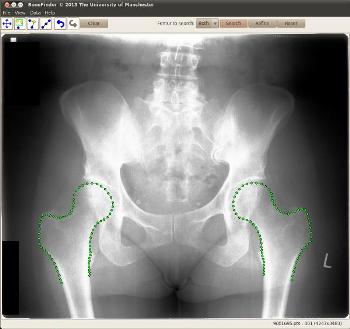

Images from BoneFinder

The system can already identify hips, but the researchers from the University’s Institute of Population Health will now adapt it to map out knees and hands and to be able to learn to identify other bones and structures within the body.

The funding of £300,000 lasts for three years and builds on earlier work which developed software, called Bonefinder, to identify problems and find the outlines of hips. This free software has been adopted by a number of research groups, including some based in Oxford and California.